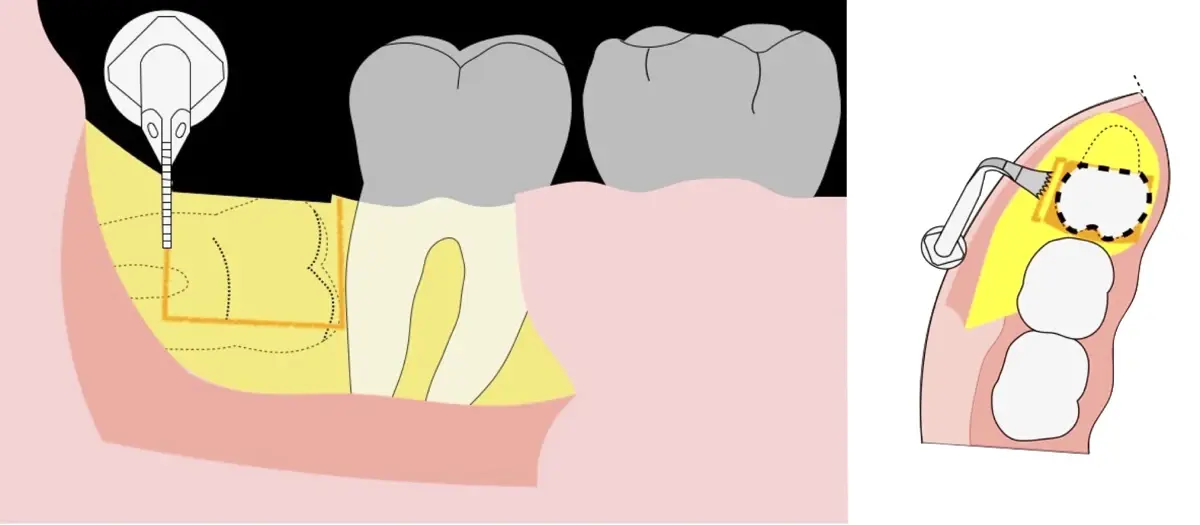

El procedimiento se inicia colocando anestesia troncular para bloqueo del nervio dentario inferior y sus ramas. Luego, se establecerá el diseño de acceso según la disposición de la molar a extraer. Para fines didácticos, se explicará cómo se realizaría la extracción de la molar de la Figura 1: se realiza una incisión horizontal a nivel de la zona retromolar hasta llegar a distal de la segunda molar, continuándose con una incisión intrasurcular hasta mesial de la segunda molar, finalizando con una incisión vertical a espesor total hasta llegar a la línea mucogingival (Figura 2).

Figura 2. Diseño de incisión para el acceso a la tercera molar.

Figura 4. Demarcación de la zona de osteotomía con insertos de corte recto y/o angulado a nivel oclusal. Vista frontal (a). Vista oclusal (b).